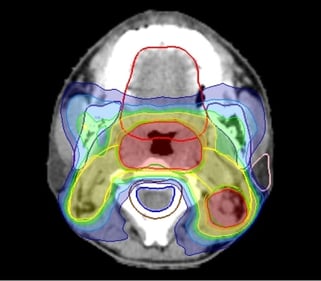

ターゲット(腫瘍)の形状が不整形で複雑な場合やリスク臓器が隣接している場合、従来の放射線照射法では腫瘍周囲の正常組織や臓器にも腫瘍と同じ線量が照射されてしまい、腫瘍制御率(腫瘍の広がりや大きくなることを抑えられた割合)を高率に維持しながら合併症を低く抑えることが困難でした。IMRTは、腫瘍に放射線を集中して照射できる革新的な照射技術です。これにより合併症を低く抑えながら根治性を高めるといった従来では実現不可能であった放射線治療が可能になりました。

IMRTに特化した装置です。腫瘍に放射線を集中させ、周辺臓器への影響を最小限に抑えることが得意であるため、腫瘍のすぐそばにリスク臓器(治療による副作用の影響を受けやすく、機能低下や障害を引き起こす可能性がある臓器)がある場合などに有用です。また、CTと同じように寝台が動くため長い範囲(食道、全脊髄など)の治療が可能です。